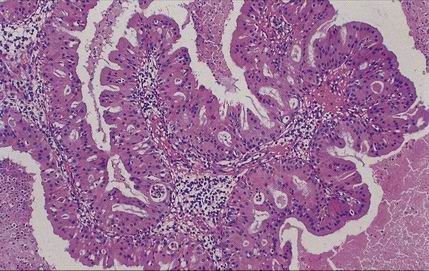

Papilomy - Schneideriánské